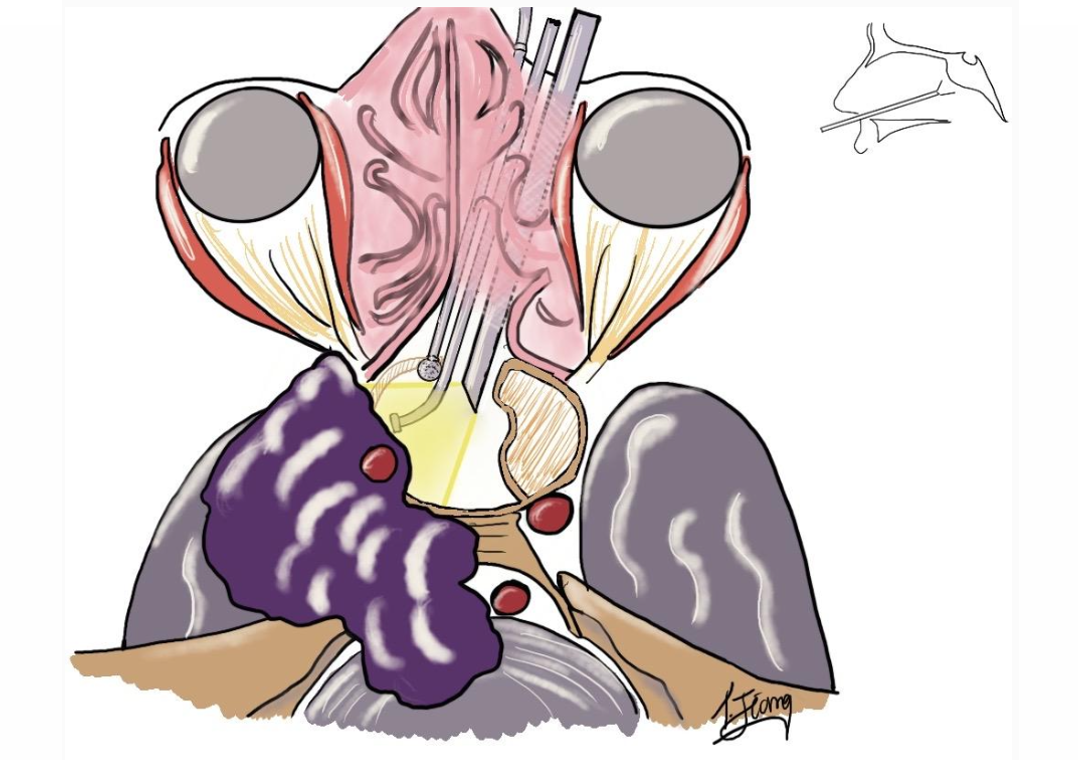

INC福教授单鼻孔操作图解

“筷子技术”,将狭小的鼻腔作为内镜和其他器械的“通道”,从而保护了鼻内部的结构,在单鼻孔狭窄的空间内也能获得360°的手术视野,将原本操作空间不足的劣势,转变为提升可操作性的优势。手指上极其微小的动作,在吸引器的尖端也能获得所需的移动幅度,从而有利于提高操作的精准度。